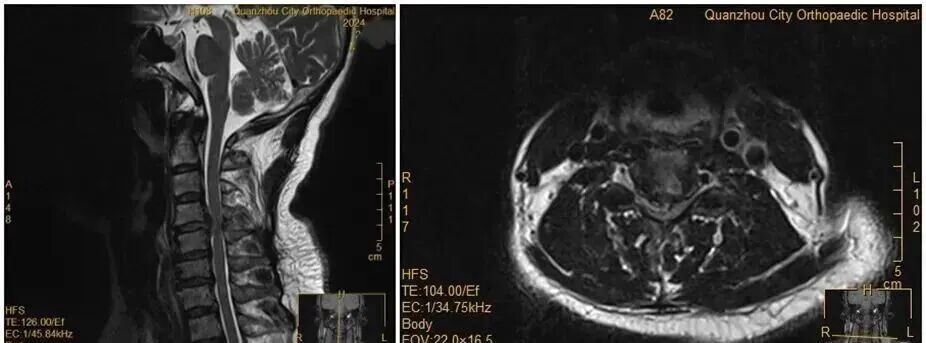

王女士術前MRI影像。圖源:第一現場

近日,福建泉州50多歲的王女士(化名)在夜里翻身想伸手拿個手機,竟突發雙上肢癱瘓,連抬手的力氣都沒有了。

沒想到,當晚在王女士翻身拿手機的瞬間,雙手突然失去知覺——關鍵肌肌力降至1級或0級,確診為癱瘓?!巴茰y是翻身時,脫出的椎間盤突然進一步卡壓到脊髓神經,引發了急性癥狀。”醫生表示。

雖然已經出現了癱瘓癥狀,但王女士仍然懼怕手術,不愿意接受手術。經過醫務團隊及王女士家人耐心解釋及勸解后,王女士才愿意接受手術治療。術后,經過一段時間恢復,她的肢體功能逐漸回歸正常。